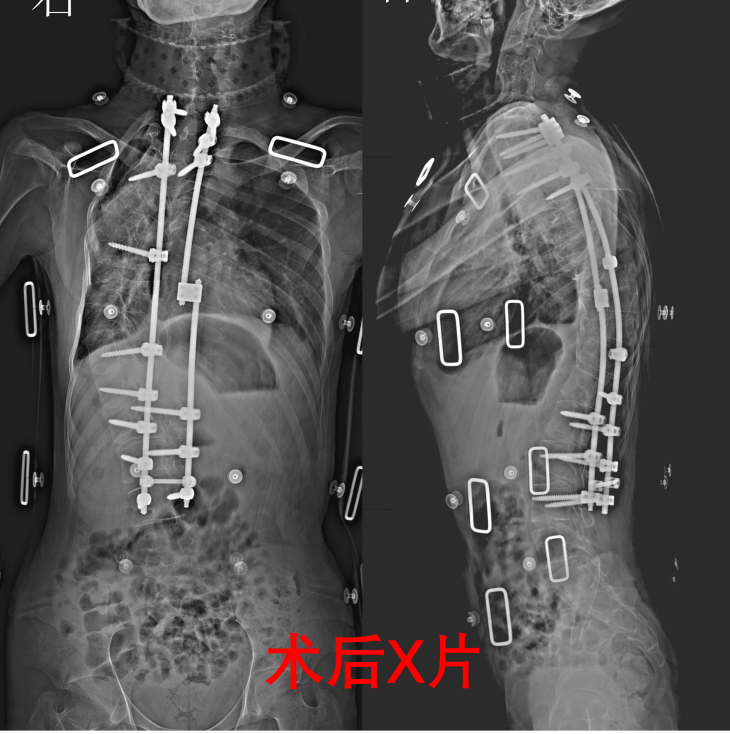

“孩子从小体弱,没有母爱,再难都要给他治。”小王的病成了他父亲的心结,16年来,带他先后前往江西、上海、北京等地求医,但都无果。经病友介绍,小王慕名找到重医附二院骨科二病区脊柱畸形团队。结合影像学结果与临床评估,团队明确:重度脊柱侧弯,脊柱侧弯角度(Cobb角)约140度,严重胸廓畸形,肺功能不全,为了保证安全,提高疗效,给小王制定头盆环牵引术、脊柱后路松解术、脊柱后路矫形术的分期治疗方案。

“脊柱后路截骨矫形植骨融合椎弓螺钉内固定术,是解决脊柱畸形最彻底的方案,但难度大、风险高。”赵登副主任医师说,患者脊柱侧弯角度大,椎体发育结构异常,不仅椎弓根螺钉植入难度大,术中稍不慎触碰脊髓或大血管,将导致瘫痪、大出血等致命风险。

几天后,楚磊教授、赵登副主任医师、张钟主治医师团队,经过7小时的奋战,顺利为小王实施手术。术后,医生团队定时查房,调整治疗方案;护理人员耐心翻身、按摩,指导康复训练;社会爱心人士每天送免费鸡蛋等,给予营养支持……经过精心治疗护理,小王康复出院测量身高时兴奋不已,“我现在163cm,比之前长高了19cm”,并送来锦旗与感谢信:“感谢医院和楚主任团队,不仅用精湛医术拯救了我的脊柱,更用暖心行动治愈了我的心灵。将来我有能力了,一定要像他们一样,帮助更多和我有同样遭遇的人!”